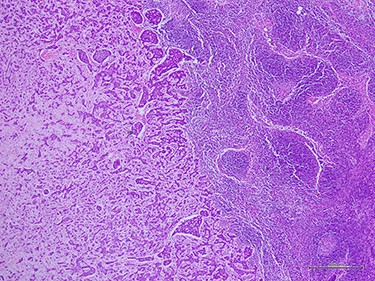

Histologic examination demonstrated metastatic ACC to axillary lymph node (40×).